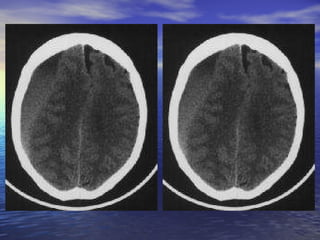

Diagnostic Imaging MRIis superior for demonstrating the size of an acute SDH and its effect on the brain, however noncontrast head CT is the primary means of making a diagnosis and suffice for immediate management purposes Noncontrast head CT scan (imaging study of choice for acute SDH) The SDH appears as a hyperdense (white) crescentic mass along the inner table of the skull, most commonly over the cerebral convexity in the parietal region. The second most common area is above the tentorium cerebelli Contrast-enhanced CT or MRI is widely recommended for imaging 48-72 hours after head injury because the lesion becomes isodense in the subacute phase In the chronic phase, the lesion becomes hypodense and is easy to appreciate on a noncontrast head CT scan

• #17 Slide #16 Subdural Hematoma Case: A 26 yo female presents to her family practice physician complaining of a headache that has persisted for over one month and sporadic blurry vision that has worsened over the last week. The headache is only slightly relieved with Ibuprofen and is worse when doing strenuous activity. The blurry vision comes and goes and can last minutes to hours when it is present. The neurologic and physical exams are normal except for some slight papilledema. The patient was then sent for a CT exam, the results of which are shown here. Diagnosis: Subdural Hematoma

• #18 Slide #17 Axial CT images of the brain show a large isodense right-sided subdural hematoma ( short arrows ) extending from the high convexities to the low frontal lobe. It is producing extensive right to left midline shift with subfalcine ( arrow )

• #19 Slide #18 and right uncal (arrow) herniation. There is trapping of the ventricles and left temporal horn with acute ependymal cerebrospinal fluid seepage, predominantly in the left periatrial and occipital regions (long arrow).